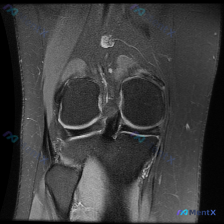

今天看到一份膝关节MRI读片的病例,问题问的是「图像里有什么类型的软骨异常」,但是整个分析下来发现其实挺容易踩坑,整理一下完整病例和思路给大家参考。 病例影像基础信息 这是单张膝关节MRI冠状位T2加权(脂肪抑制)图像,图像对比度良好,解剖结构清晰,没有明显伪影,完整覆盖了股骨髁、胫骨平台、内外侧副...

看到这个膝关节MRI的病例,整理了资料和分析思路分享给大家。 病例影像资料 这是一张膝关节冠状位MRI图像(考虑为质子密度加权像或T2加权像,对积液和软组织病变显示更敏感),影像所见核心信息如下: 1. 骨性结构:股骨远端、胫骨近端骨皮质完整,无明显骨折或骨质破坏,内外侧胫骨平台关节软骨下骨边界清晰...